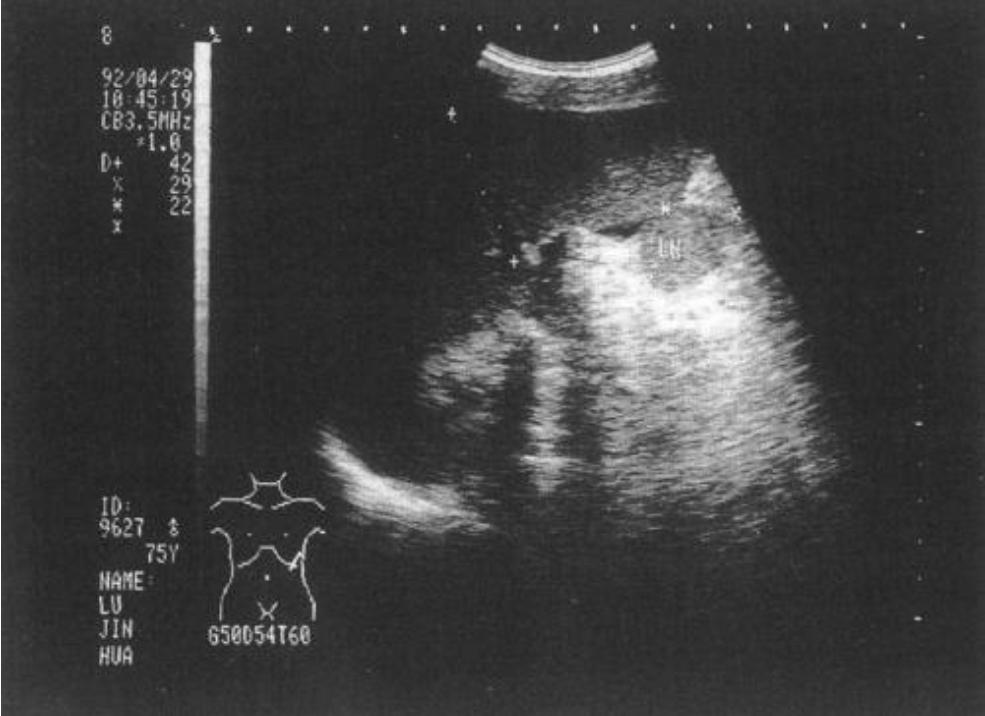

妇产科的超声检查主要有两类:腹部超声和阴道超声。

顾名思义,腹部超声,是利用探头直接经过腹部探测,仔细观察子宫及双附件。是门诊开具的检查中,使用较高的一种检查方式。

经腹部的超声需要膀胱充盈,也就是俗称的“憋尿”,否则图像质量会有影响,同时因为每个人腹部脂肪层等情况不同,可能会影响超声检查的结果,这是经腹部超声的局限,但因为其扫查范围广,对比较大的占位性病变有优势。

此种检查是经过阴道通过探头来取得超声影像,经阴道超声是通过将探头套上一层保护膜,然后放入阴道内检查子宫及双附件,适用于有过*生活性**的女性。

优点是无需憋尿,且因其使用高频探头,这种观察方式更清晰,诊断更精确,能检查到一些较为小的病变影像。许多婚龄女性更偏爱此种检查,无需等待,且筛查更准确。